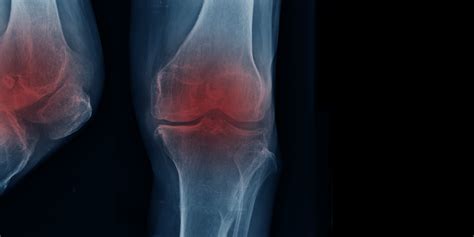

Let’s zero in on osteoarthritis (OA) first, because it’s the most common type, affecting millions of people worldwide. Think of your joints like a well-oiled machine with shock absorbers. In OA, the protective cartilage that cushions the ends of your bones gradually wears down. Over time, this can lead to bone rubbing against bone, causing that characteristic pain, stiffness, and reduced flexibility. While OA often affects weight-bearing joints like knees, hips, and spine, it can also impact hands and other joints. For many, OA starts subtly, but as it progresses, the pain becomes more constant and severe. This can make simple tasks incredibly difficult. Imagine trying to stand for long periods, walk to the grocery store, or even just grip a pen to write. When the joints involved are critical for your job – say, you’re a construction worker, a nurse, or a retail associate who spends hours on their feet – OA can quickly make your job impossible. The physical demands of many occupations become insurmountable, leading individuals to consider disability. The long-term effects of OA can include chronic pain that doesn’t respond well to medication, joint deformities that further restrict movement, and significant loss of mobility. This isn’t something that just goes away; it’s a chronic condition that often requires ongoing management and can significantly impact your quality of life, pushing many towards seeking disability support because their capacity to work and function is severely compromised.